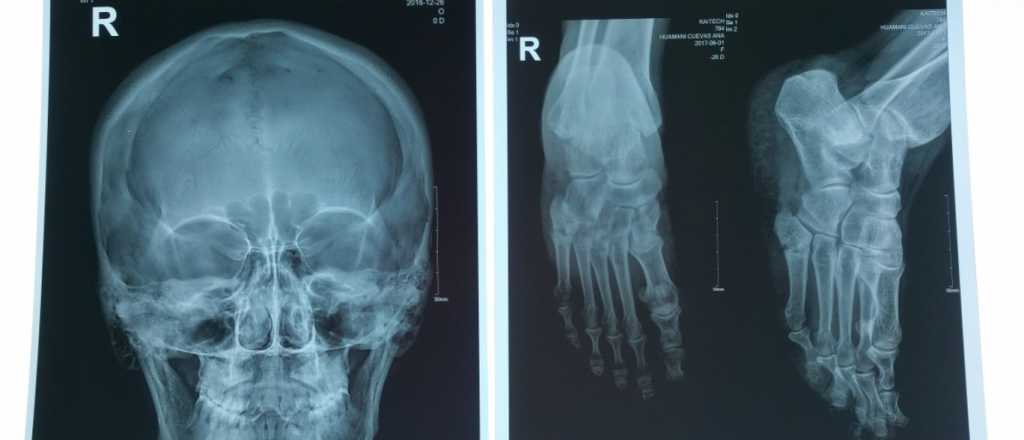

En un primer momento, los Rayos X eran utilizados para poder observar y analizar los huesos y pulmones sobre una superficie gris pero, con el avance de la tecnología, se empezaron a usan para poder estudiar de forma íntegra el cuerpo humano.